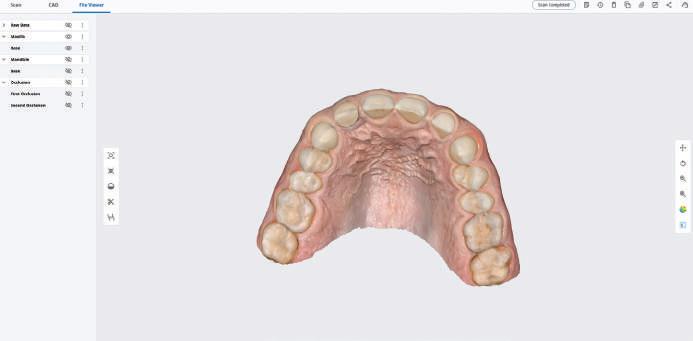

След диагностиката бяха направени екстра- и интраорални снимки, както и рентгенографии; професионалното почистване бе от изключителна важ ност, бяха дадени и инструкции за лич на орална хигиена. Бе направено интра орално сканиране с Medit i500. Цялата тази информация бе използ вана в приложението Smilecloud за 2D биометричен дизайн. В приложението са налични естест вени форми на зъбите и щом бяха под брани зъби и бе направен дизайн

библиотеката на Exocad. Струва си да се отбележи, че 2D дизайнът от Smile Cloud бе спазен до последния детайл в Exocad smile creator с цел да се създаде 3D obj файл със зъбните форми. След като естетичният дизайн бе готов в model creator модула на Exocad, адитивен 3D мок-ъп модел бе експорти ран и принтиран от принтер Formlabs 3. Моделът бе използван за направата на силиконов водач, за да се изготви мо тивационен мок-ъп в устата на паци ента и да се оценят естетичните па раметри. След като пациентът одобри вида на усмивката си, мок-ъпът бе използван за финализиране дизайна на усмивка та. Мок-ъпът бе използван също така като водач по време на мекотъканна та хирургия, както и при препарация на зъбите.

Препарираните зъби бяха импорти рани в Exocad и насложени върху ес тествените форми от биометричния дизайн, като така стана ясно дали зъ бите са били препарирани коректно. По този начин зъболекарят и зъботехни кът работят в една и съща екосистема и резултатът е оптимален. С короната се справихме чрез диги тална редукция на циркония в Exocad, като по този начин на практика създа дохме циркониево кепе, след което про изведохме фасета от IPS Empress Cad Multi. Кепето от Katana Zirconia на зъб 12 с букално послойно нанесена керами ка бе фрезовано (послойното нанасяне бе направено, за да се подобри връзката и да се осигури адхезивно циментиране на фасетата към циркониевото кепе, както и за да се напасне цветът към този на съседните зъби). При първото сканиране регистрирах ме цялата горна зъбна дъга, така че, ко гато се наложи да сканираме повторно, бе изтрит и сканиран наново само зъб 12, тъй като венците не бяха отдръп нати при второто сканиране.

рентгенографии. Инициална терапия и професионално почистване. Интраорално сканиране с цел диги тално планиране. Регистрация и 3D ориентиране на ок лузалната равнина на горна и долна челюст в пространството. 2D дигитално планиране и дизайн на усмивката посредством приложение то Smile Cloud. 3D дигитално планиране и дизайн на функционалните и естетичните па раметри. 3D дигитален дизайн и адитивен мокъп на горна челюст. 3D принтиране и мок-ъп модели. Мотивационен мок-ъп. Фини корекции за постигане на фи налния дизайн. Мекотъканна хирургия с мок-ъпа като водач Препарация през мок-ъпа, използвай ки дизайна като водач за финалната препарация в Exocad. Циркониево кепе ще бъде циментира но с цел адхезивно залепяне на фасе та на края. Кепето има същия цвят като този на съседните зъби, за да може фасетата да се впише перфект но в цялостната усмивка. Изработване на 12 IPS Empress Cad Multi фасети с послойно нанесена ке ТОТАЛНА РЕХАБИЛИТАЦИЯ НА УСМИВКАТА С ИЗЦЯЛО ДИГИТАЛЕН ПРОТОКОЛ Д-р Калин Маринов и зт. Стефан Петров рамика букално върху зъбните препа рации и върху първичното циркони ево кепе (има възможност за ецване и адхезивно

Една седмица след препарацията на зъбите и циментирането на цирко ниевото кепе бяха изработени 12 IPS Empress Cad Multi фасети. Макро- и микротекстурата на фасе тите бяха направени на ръка, след кое то бяха нанесени 3D характеризации с боички, а полирането отново бе напра вено ръчно, за да им се придаде естест вен и естетичен вид. Предизвикателството тук беше короната да има същите оптични характеристики като тези на остана лите зъби при естествена светлина, през поляризационен и флуоресцентен филтър. 3D принтерът бе Fromlabs, софтуерът за фрезоване – Mill Box, а фрез апаратът –imes icore CORiTEC 350i. В крайна сметка постигнахме ес тествен вид на усмивката с натурал на зъбна морфология при изцяло диги тален протокол, при който дизайнът бе направен първоначално и през всич ки етапи на лечението се придържахме към него до самия край Излишно е да отбелязваме, че всички сме удовлетворени от постигнатото! Преди След Победител в категория „Клиничен случай с изцяло дигитален протокол“ в конкурса „Усмивка на годината 2022“